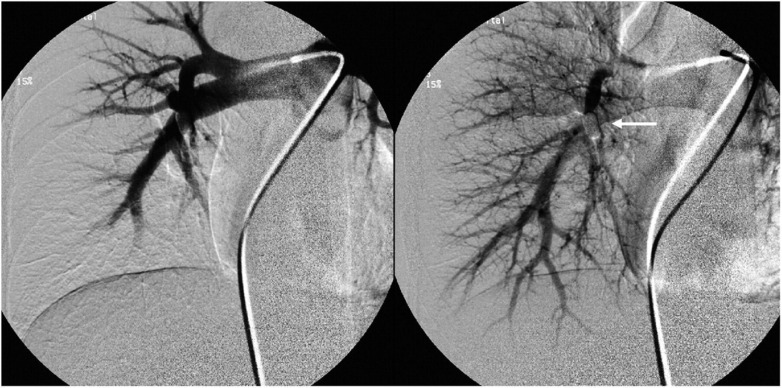

肺动脉动静脉畸形(pavm)的供血动脉长度为3mm或以上,已被证明与矛盾栓塞和严重的神经系统并发症有关。因此,通常建议闭塞这种大小的供血动脉,而较小的供血动脉通常不予治疗。然而,神经系统并发症也被描述在小的pavm患者中,并且不可能根据供血动脉的大小对风险进行分层,因此没有证据表明3mm是可能引起并发症的供血动脉的临界大小。此外,众所周知,随着时间的推移,pavm及其供血动脉可能会扩大。此外,栓塞小供血动脉将最大限度地减少矛盾栓塞的风险,并减少对这些患者进行CT随访控制的需要。两个病例证明了栓塞小供血动脉的可能性。

Pulmonary arteriovenous malformations (PAVMs) with feeding arteries of 3 mm or more have been shown to be associated with paradoxical embolization and serious neurologic complications. Therefore it is generally recommended to occlude feeding arteries of this size, while smaller feeding arteries often are left untreated. However, neurologic complications have also been described in patients with small PAVMs, and it has not been possible to stratify risk by size of feeding artery and thus there is no evidence that 3 mm is the critical size of the feeding artery potentially giving complications. Further, it is well-known that with time PAVMs and their feeding arteries may enlarge. Also, embolization of small feeding arteries will minimize the risk of paradoxical emboli and reduce the need for CT follow-up controls in these patients. Two cases demonstrate the possibility to embolize small feeding arteries.